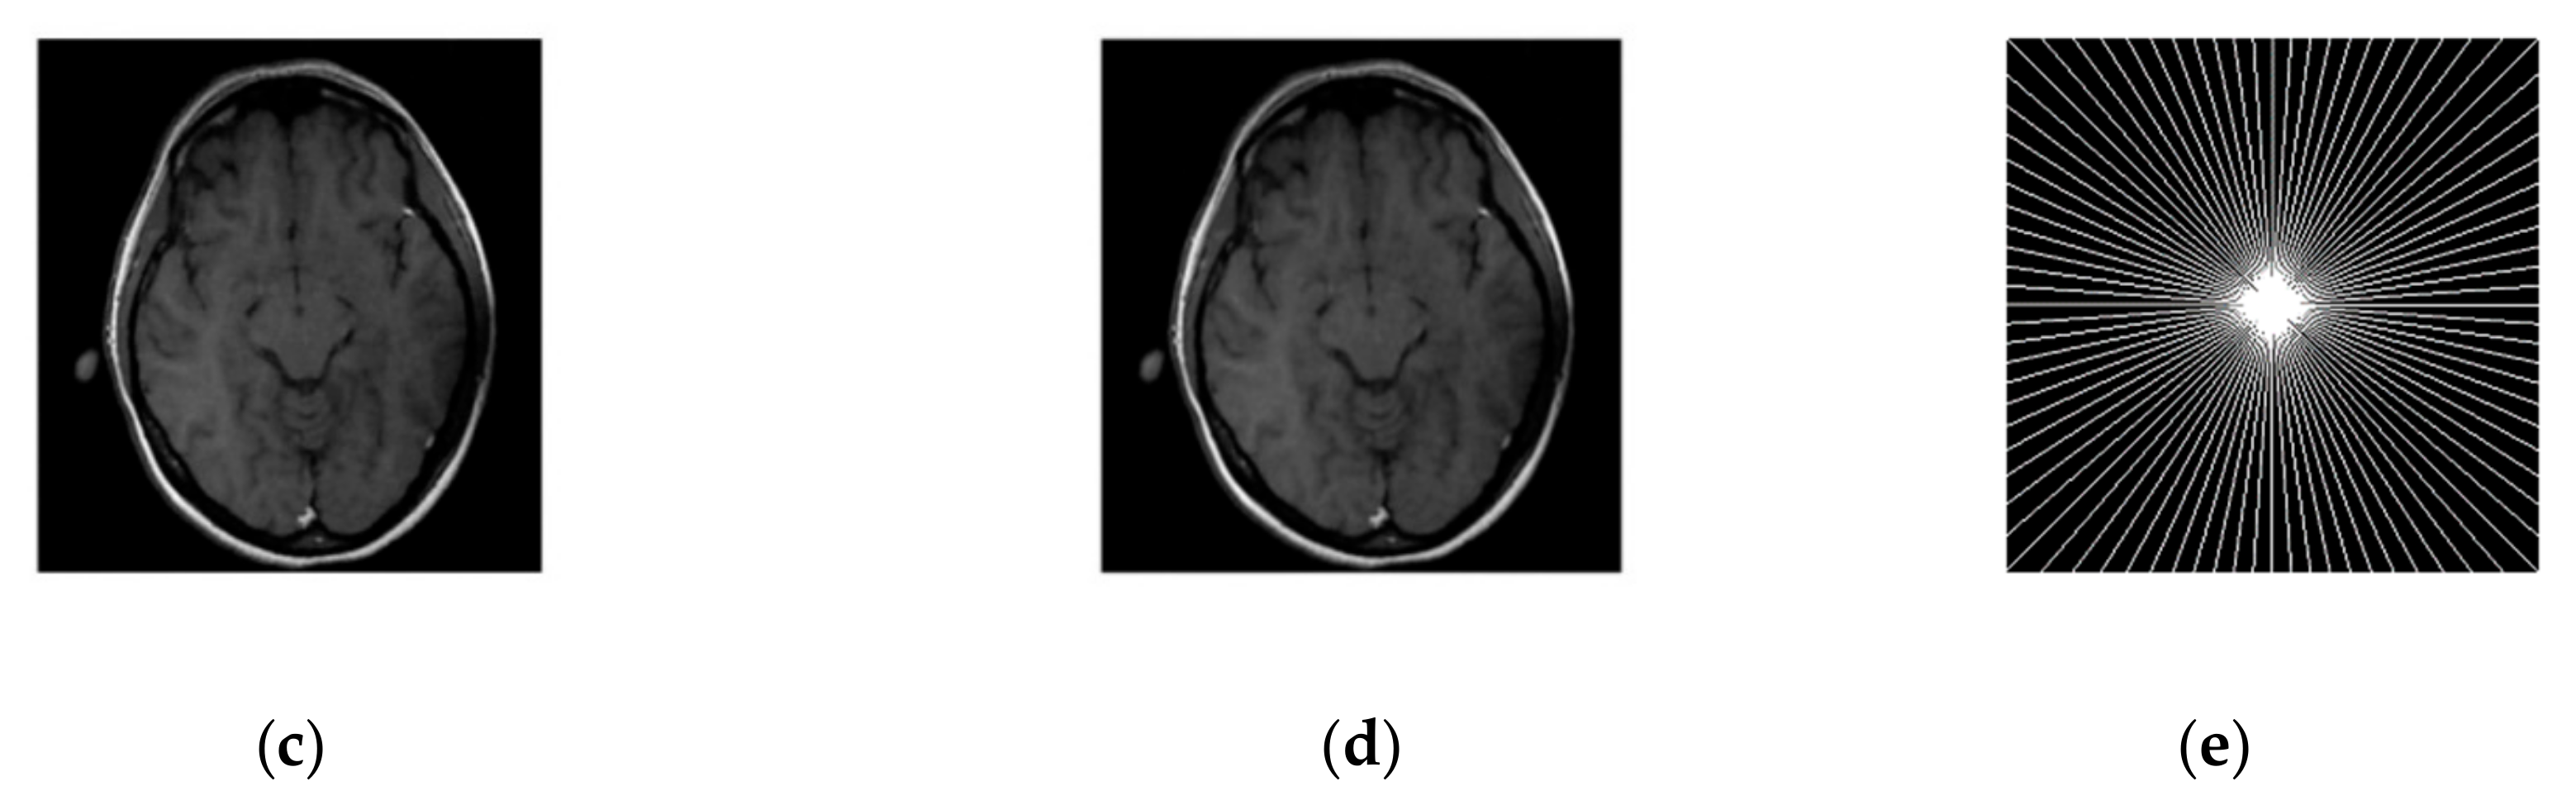

Figure 5. Algorithms performance in noisy case with cartesian sampling. (a) PSNR vs iterations with comparison to DLMRI for a phantom image (b) HFEN vs iterations with comparison to DLMRI for a phantom image (c) Cartesian sampling scheme with 4 fold. (d) Recovered image.

Graphs in Figure 5a,b are shown for a noisy case with 4 fold Cartesian under sampling for reconstruction of a phantom image.